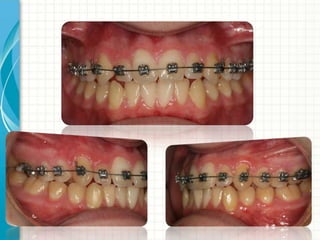

Nickel Titanium wires

Use of Nickel Titanium

• Initial Alignment

• Correction of rotations

• Torque control

Most popular sizes for NiTi

Size Contact information

O.014 round Initial alignment

0.016-0.018 round Completion of alignment

Rotations

0.016x0.022 Complete alignment

Torque initiation

0.018x0.025 Completion of torque

Pre expansion